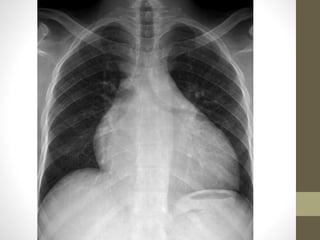

HCM DIAGNOSIS 2

• CXR-

• LV enlargement

• LA RA enlargement

• PAH